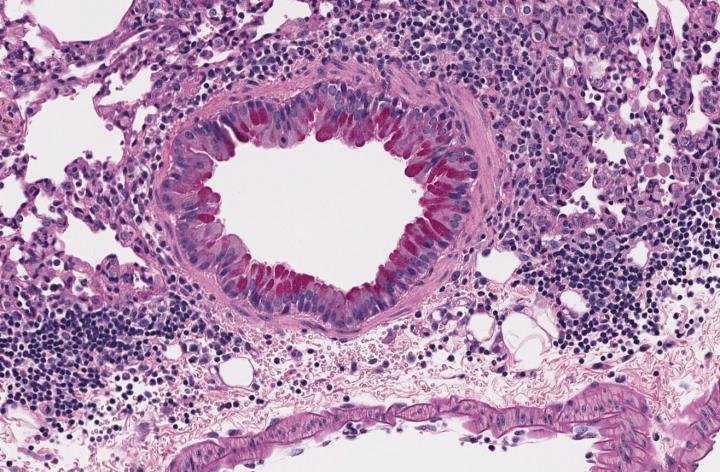

In the new study, Underhill and colleagues observed that the expansion of a certain species of house dust fungus (Wallemia mellicola) can occur in the intestines of mice after they are treated with antibiotics and exposed to the fungus. By contrast, mice with an intact and healthy intestinal microbiota resist this expansion. After expansion of this fungal population, the mice are more prone to develop asthma-like inflammation in their lungs when exposed to allergens. Although it is not known whether the same phenomenon can occur in people with asthma, the researchers also show this fungus is a component of the microbiota of some healthy humans.